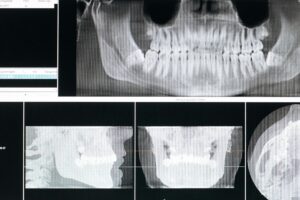

TMJ disorder is diagnosed through a combination of medical history reviews and a physical exam of the jaw. Your dentist will check jaw motion, listen for joint sounds, and assess any muscle tenderness. They might also ask about habits like teeth grinding or clenching, stress levels, and any changes in your bite. Imaging tests like X-rays may be used if there is a need to see the joint details more clearly.